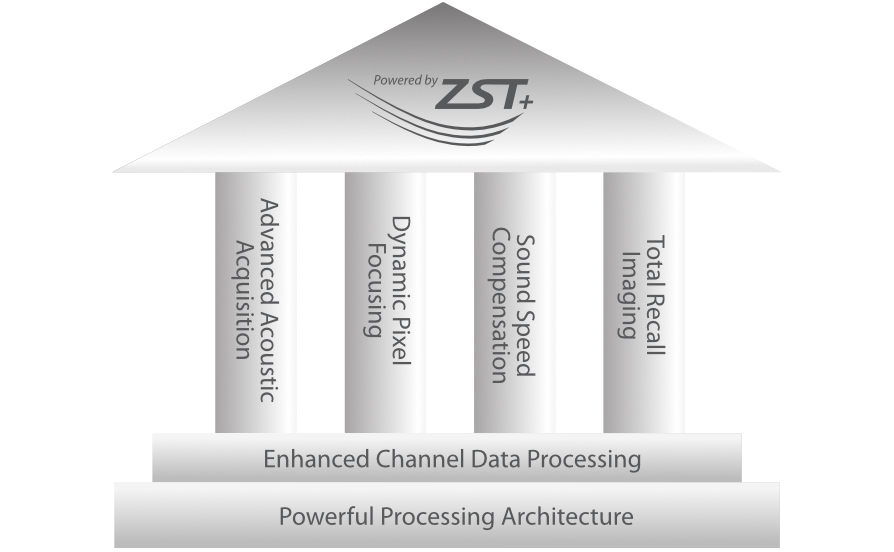

Solution complÃĻte gr?ce au ZST +

La plate-forme ZST+?est une innovation extraordinaire, reprÃĐsentant une ÃĐvolution de lâimagerie ultrasonore. Elle transforme la formation conventionnelle de faisceaux en un traitement basÃĐ sur les canaux de donnÃĐes. Elle repousse les limites de lâimagerie conventionnelle et du compromis entre rÃĐsolution spatiale, rÃĐsolution temporelle et uniformitÃĐ tissulaire en offrant une qualitÃĐ dâimage exceptionnelle pour des solutions dâimagerie infinies et en constante ÃĐvolution.